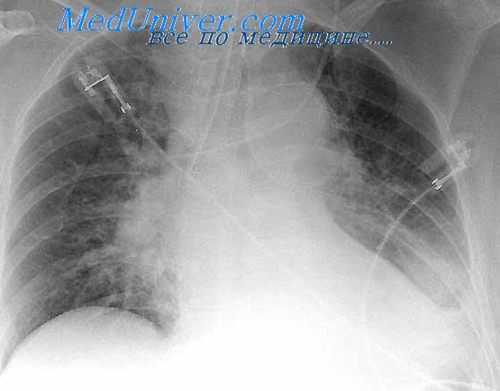

У ряда больных раком легкого бронхоспирометрия выявляет полное отсутствие поглощения кислорода в пораженном легком при сохранении вентиляции в нем. Этот признак обычно сочетается со следующими симптомами, выявляемыми при рентгенологическом исследовании:

1) наличие пакетов лимфатических узлов в области корня легкого;

2) расширение и уплотнение корня;

3) слияние тени центрально расположенной опухоли с тенью корня;

4) обеднение сосудистого рисунка пораженного легкого.

Сочетание отсутствия поглощения кислорода в легком, пораженном раковой опухолью, с одним или несколькими из перечисленных рентгенологических симптомов дает возможность говорить о синдроме обструкции магистральных легочных сосудов и может служить указанием на неоперабельность (А. В. Григорян, Б. П. Федоров и С. В. Лохвицкий, 1966).